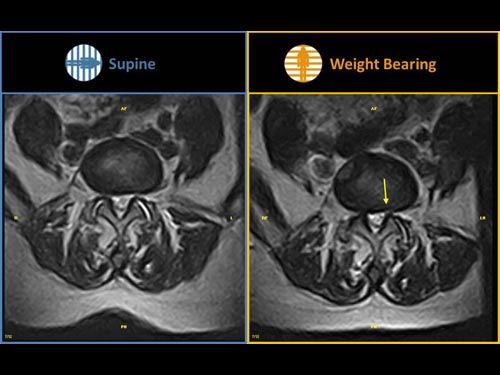

Nová končetinová magnetická rezonance G-scan Brio od společnosti Esaote je tomografický systém MRI, který umožňuje studium všech kloubů i páteře, ať už v klinostatické (vleže) nebo ortostatické (vážící) poloze, protože magnet i pacient se mohou otáčet od 0 do 90 stupňů. Díky inovativnímu designu G-scan mohou být pacienti Brio skenováni v poloze nesoucí váhu, aby se usnadnila diagnostika MSK u těch patologií, které se mohou měnit v důsledku držení těla a polohy, jako jsou bolesti dolní části zad.

• Váhové ložisko: poloha pacienta se stává nedílnou součástí výsledku vyšetření

• Další diagnostické schopnosti: jelikož gravitační síla generuje bio-mechanické změny v anatomii, MR zobrazení v přirozené poloze ve stoje vám umožňuje dosáhnout důležitých dalších informací ve srovnání s tradičními MRI

Klinické snímky